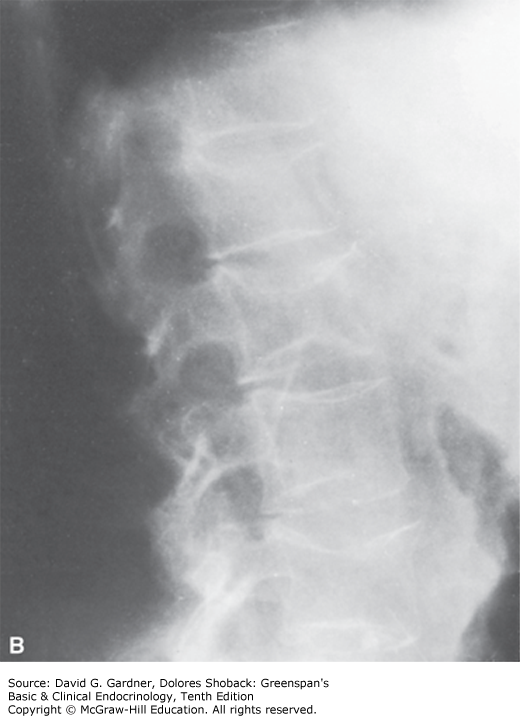

A. Magnified x-rays of thoracic vertebrae from a woman with osteoporosis. Note the relative prominence of vertical trabeculae and the absence of horizontal trabeculae. B. Lateral x-ray of the lumbar spine of a woman with postmenopausal osteoporosis. Note the increased density of the superior and inferior cortical margins of vertebrae, the marked demineralization of vertebral bodies, and the central compression of articular surfaces of vertebral bodies by intervertebral disks. (Used with permission from Dr. G. Gordan.)